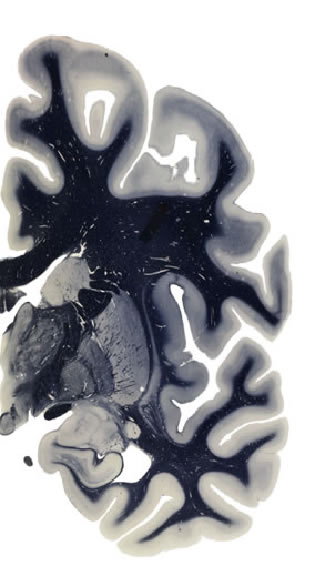

Hi-Resolution Sections · Cells (Nissl Staining) · Virtual Microscopy

Frontal sections (Nissl) from the Atlas Brain:

Slice ID:

r3-1059

Plate NR:

ca 29

Position:

9,2 mm